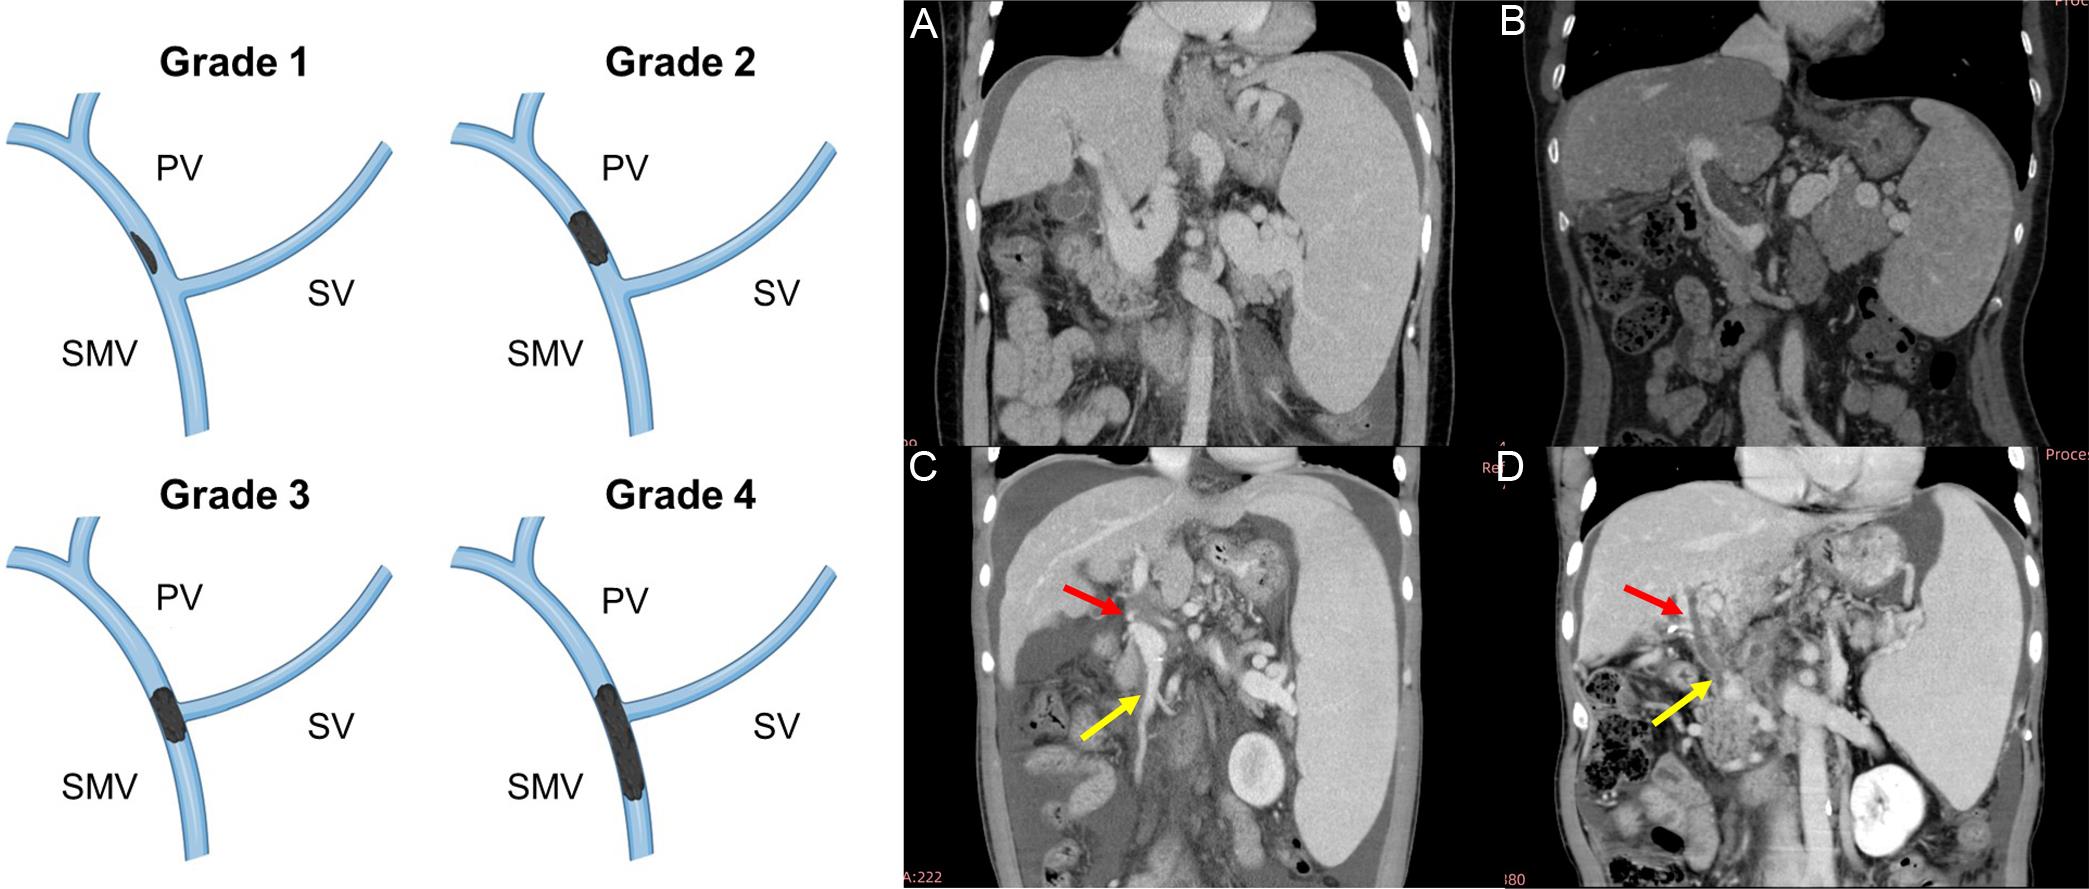

Among the 169 patients, 156 (92.3%) underwent contrast-enhanced CT, and 13 (7.7%) underwent MRI. PVT was diagnosed in 45 (26.6%) patients at baseline. Of these, 10 (22.2%), 17 (37.8%), two (4.4%), and six (13.3%) had Yerdel grades 1, 2, 3, and 4, respectively (Fig. 2). The remaining 10 patients could not be classified using the Yerdel system because thrombosis was limited to branches of the portal vein, SV, or SMV.

Yerdel classification of portal vein thrombosis.

Fig. 2  Yerdel classification of portal vein thrombosis.

A: grade 1, < 50% occlusion of the main portal vein (PV) with no or minimal obstruction of the superior mesenteric vein (SMV, top left of left panel); B: grade 2, > 50% obstruction of main PV, including total obstruction (top right of left panel); C: grade 3, complete obstruction of main PV and proximal SMV (bottom left of left panel); D: grade 4, complete obstruction of the PV and SMV (bottom right of left panel). Red arrow: thrombosis in the PV; yellow arrow: thrombosis in the SMV. SV, splenic vein.